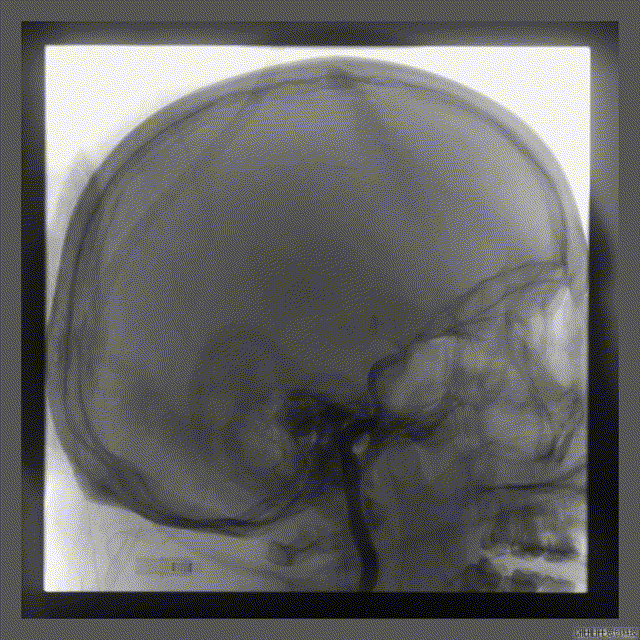

NUMEN Case 6

NUMEN Case 8